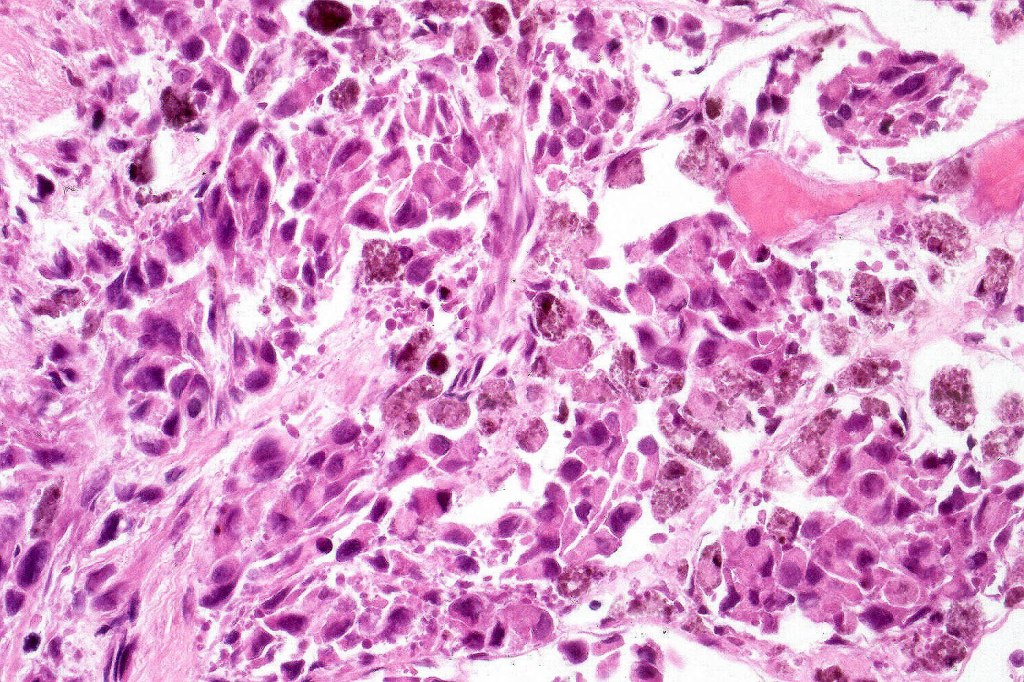

Melanoma with osteoid and chondroid (benign or malignant) are most often encountered in the digits particularly the thumb and large toe, for the other types, they are too rare to make any meaningful clinical comments. Documented heterologous elements include: